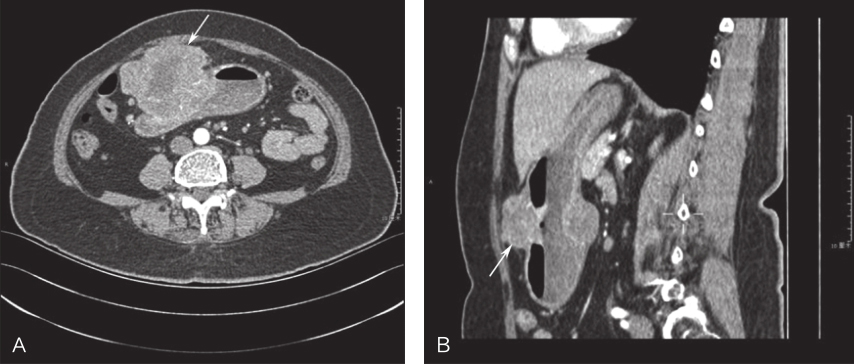

上腹部增强CT:肝胃间隙见大小约11.2cm×11.4cm软组织肿块影,呈多发分叶状,密度不均,考虑间叶源性肿瘤可能性大(图2)。

图2腹部CT提示肝胃间隙巨大分叶状软组织肿块影

A.横断位;B.矢状位